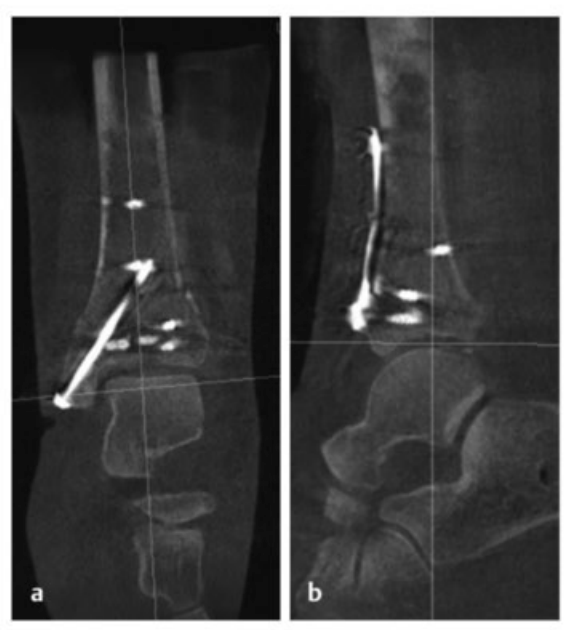

术中三维CT 扫描确认骨折达到解剖复位,内植物位置良好。术后影像学检查证实骨折解剖复位,内植物位置正常。患者术后恢复过程顺利,关节功能恢复良好。

典型病例 2

病例2受伤后入院首先植入跨踝关节外固定架,待软组织肿胀消退后,先对腓骨骨折进行微创固定,随后逐步完成复杂的胫骨Pilon骨折复位与固定。

术中临床图像显示了损伤的严重程度,同时体现了微创手术技术的优势,以及在必要时下胫腓联合切开复位重建的重要性。借助斯氏针的 “操纵杆(Joy-Stick)” 技术,可显著简化关节面的复位操作。

术后影像学随访检查显示骨折解剖复位,内植物位置良好。

患者术后恢复顺利,关节功能良好。术后12个月取出内植物,未发现创伤后关节炎征象。